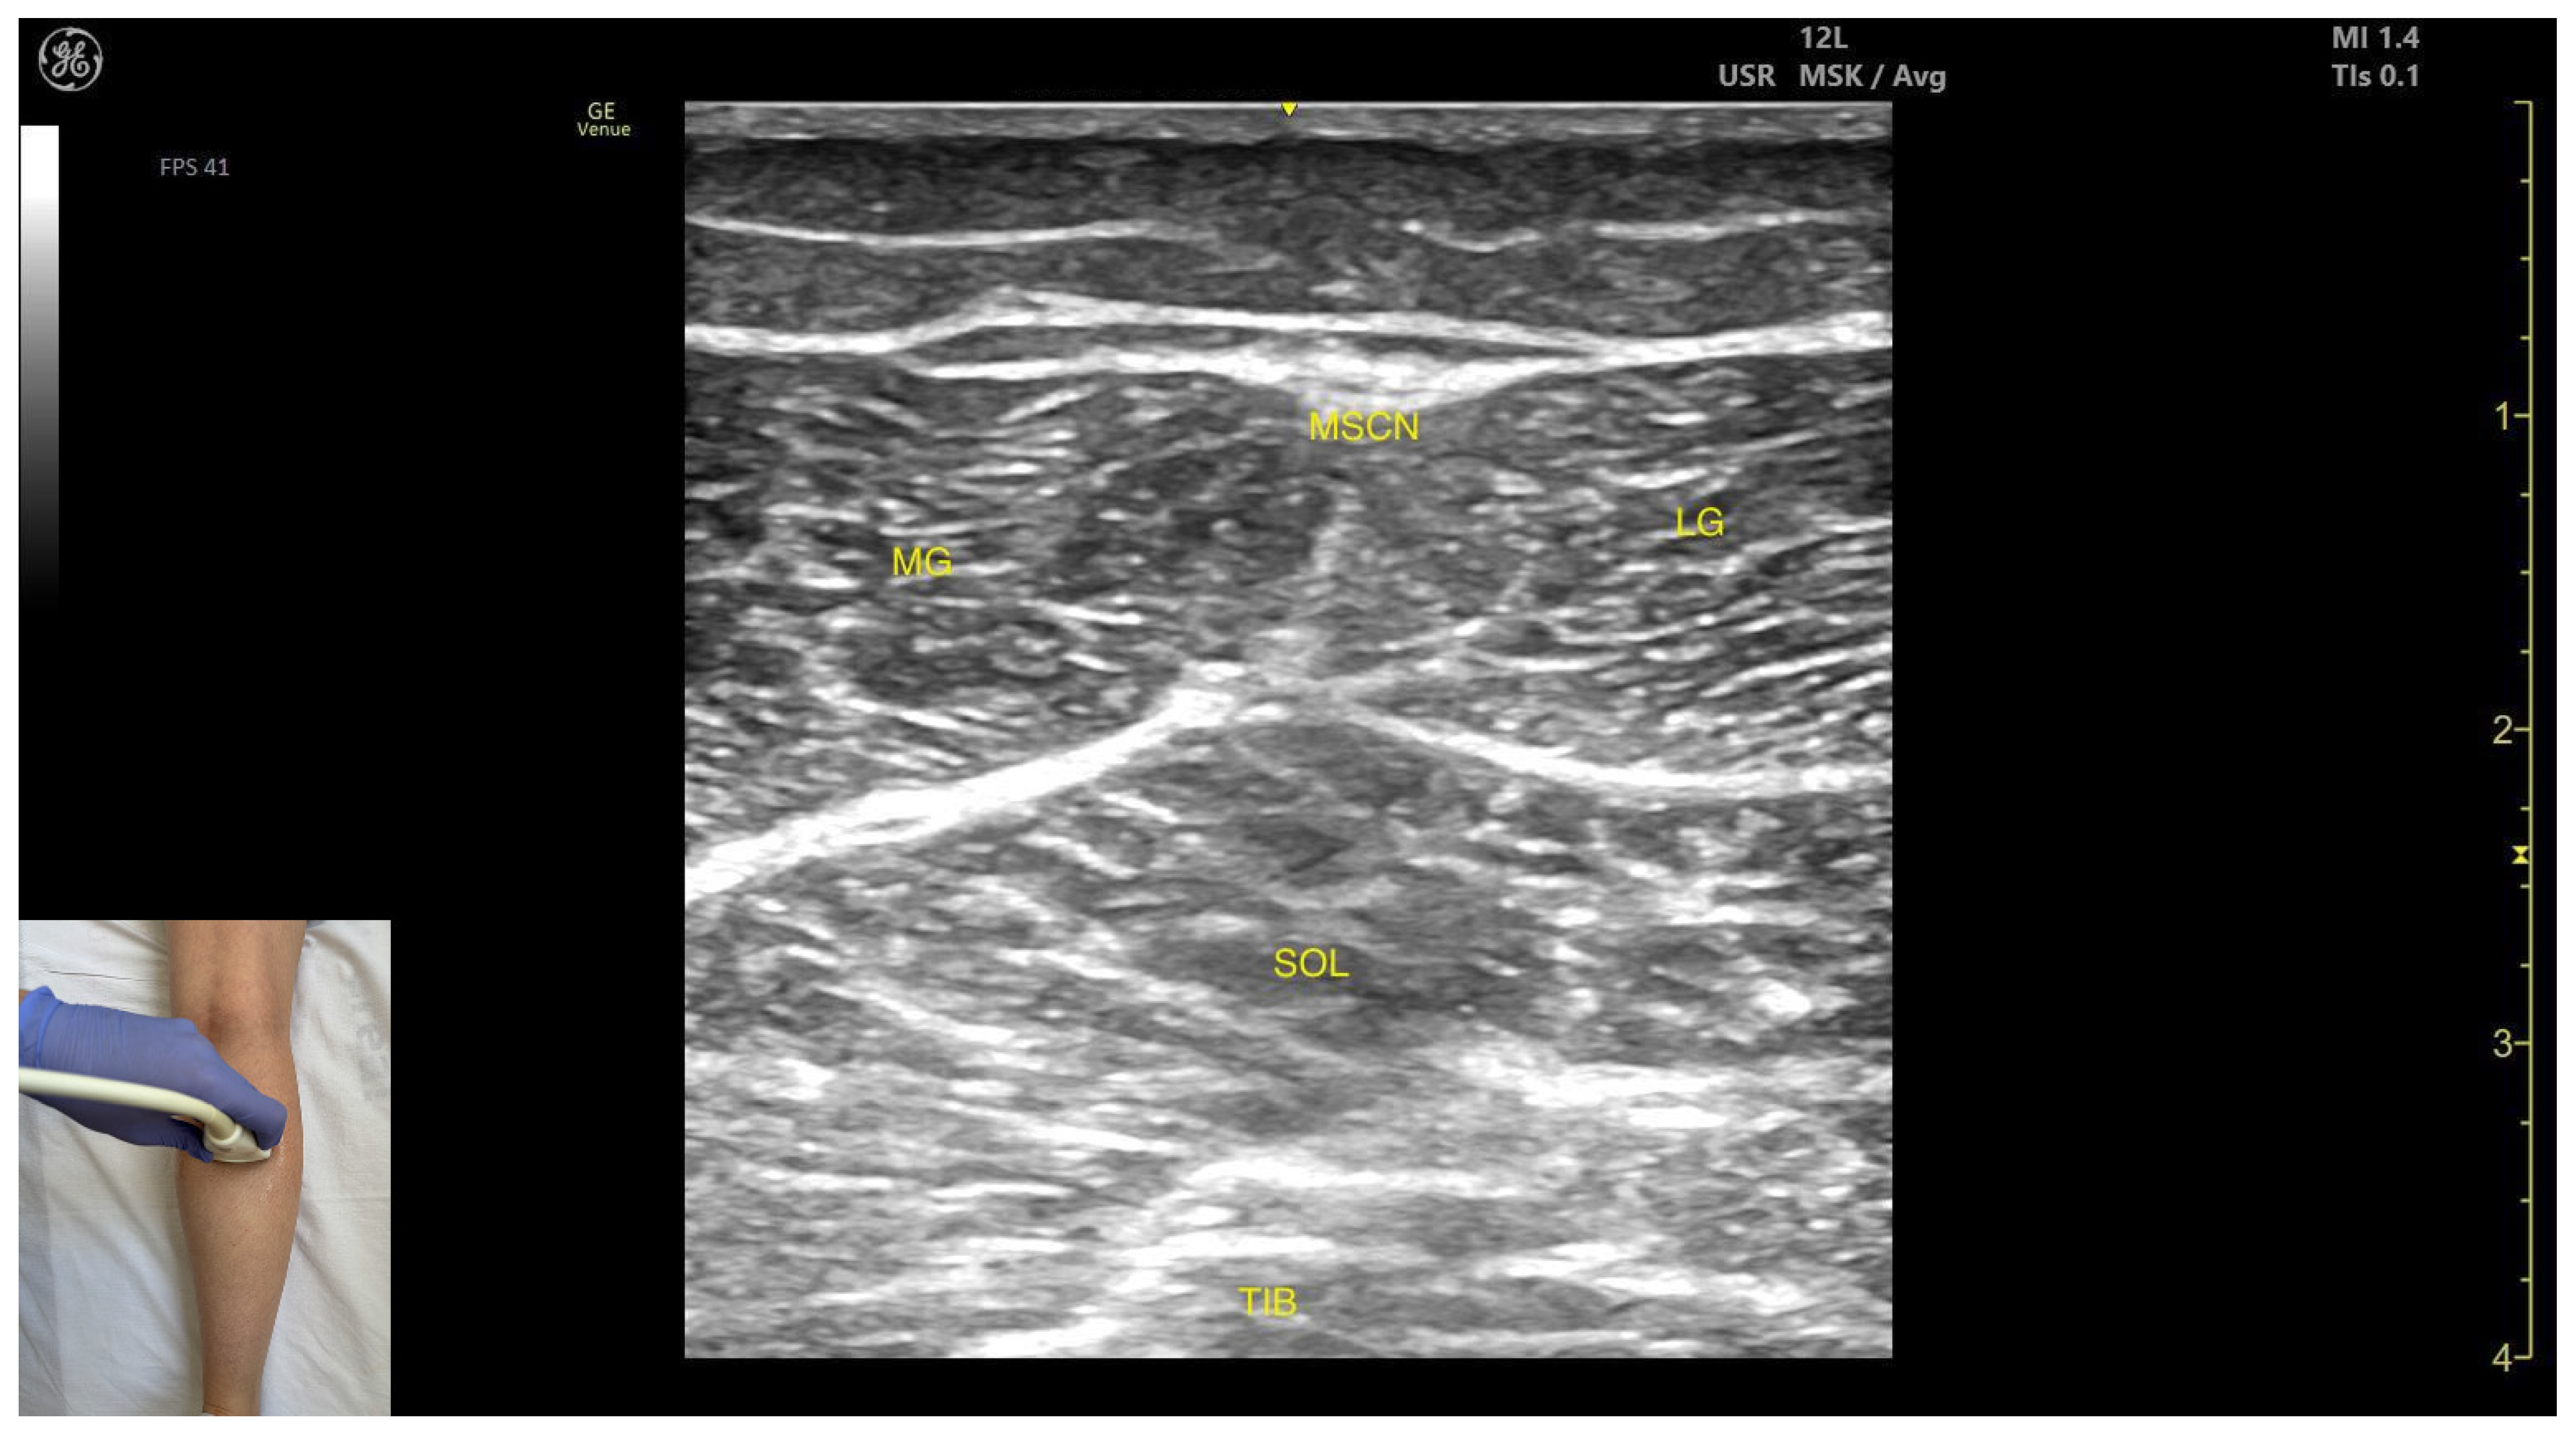

- Muscle position: It is the most superficial and prominent muscle in the posterior compartment of the leg, and one of the largest in the region. The soleus—and, if present, the plantaris—is located deep to it.

- External fascia: It presents a well-defined fascia separating it from the subcutaneous plane, soleus, and plantaris muscle/tendon, during BoNT-A injection.

- Dynamic evaluation: During dynamic evaluation, scanning toward the ankle joint, the lateral head of the gastrocnemius progressively decreases and eventually disappears while the soleus increases in thickness; distally, both merge into the Achilles tendon with the soleus (and plantaris, if present). On medial scanning the intersection of the lateral and medial gastrocnemius heads is visualized—the medial sural cutaneous nerve typically courses between these heads. Because the gastrocnemius is a biarticular muscle crossing both the knee and ankle joints, it is assessed with the knee extended to place the muscle on maximal stretch and thereby reveal its contribution to ankle plantarflexion. Muscle contraction is visible during plantar flexion of the foot at the ankle joint, as well as during knee flexion.

- Muscle position: It is the most superficial and prominent, and of the largest muscles in the posterior compartment of the leg. The soleus—and if present, the plantaris—is located deep to it.

- Muscle morphology: The medial head of the gastrocnemius is larger and extends more distally than the lateral head of the gastrocnemius.

- External fascia: It presents a well-defined fascia separating it from the subcutaneous plane, soleus, and plantaris muscle/tendon aiding in safe BoNT-A injection.

- Dynamic evaluation: During dynamic evaluation, scanning toward the ankle joint reveals the medial head of the gastrocnemius progressively decreases and eventually disappears while the soleus increases in thickness; further distally, both converge to form the calcaneal (Achilles) tendon, often with the plantaris tendon interposed when present. On lateral scanning the intersection of the medial and lateral gastrocnemius heads is visualized—the medial sural cutaneous nerve typically courses between these heads. The gastrocnemius, spanning both the knee and ankle joints as a biarticular muscle, is evaluated with the knee fully extended to place it under maximal longitudinal tension, thereby accentuating its functional role in ankle plantarflexion. Contraction is visible during plantar flexion of the foot at the ankle joint, as well as during knee flexion.

- Muscle morphology: It appears as a flat muscle in the posterior compartment of the leg.

- Muscle position: At this level, the soleus lies deep to the intersection of the gastrocnemius heads, within which the medial sural cutaneous nerve courses.

- External fascia: A pronounced fascia separates it from the subcutaneous plane, gastrocnemius muscles, and the plantaris muscle/tendon (if present), which is relevant during BoNT-A injection.

- Dynamic evaluation: During dynamic evaluation, scanning laterally reveals enlargement of the lateral gastrocnemius head, and deep to the soleus, the neurovascular bundle emerges, comprising the posterior tibial artery, the two posterior tibial veins, and the posterior tibial nerve. Medial scanning highlights enlargement of the medial head of the gastrocnemius (MG), while the neurovascular bundle maintains its anatomical course. The soleus, a monoarticular muscle acting exclusively at the ankle joint, is optimally assessed with the knee flexed; this positioning diminishes gastrocnemius involvement, allowing for isolated evaluation of soleus contractile activity via EMG or dynamic ultrasound imaging. Muscle contraction is visible during plantar flexion maneuvers of the foot at the ankle joint.

| Lateral Head of Gastrocnemius | ~8 cm distal to the popliteal crease, on the lateral side | Medial sural cutaneous nerve (superficial), soleus and plantaris muscle/tendon if present (deep) | Transverse scan on the posterior aspect of the leg | Avoid medial sural cutaneous nerve injury |

| Medial Head of Gastrocnemius | ~8 cm distal to the popliteal crease, on the medial side | Medial sural cutaneous nerve (superficial), soleus and plantaris muscle/tendon if present (deep) | Transverse scan on the posterior aspect of the leg | Avoid medial sural cutaneous nerve injury |

| Soleus | ~8 cm distal to the popliteal crease on the midline | Gastrocnemius (superficial) and plantaris muscle/tendon (if present); posterior tibial artery, tibial veins, and the posterior tibial nerve (deep) | Transverse scan on the posterior aspect of the leg | Avoid neurovascular injury |